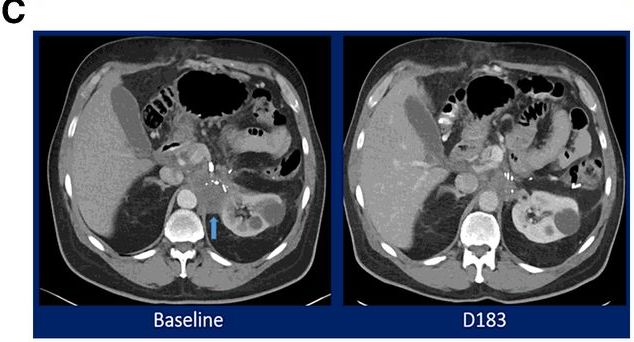

49岁HPV感染阳性的女性转移性宫颈癌患者,在接受顺铂/紫杉醇后加贝伐单抗治疗,随后病情进展,出现两个病理性扩大的纵隔淋巴结(图左侧箭头)。入组M7824的临床试验后,在用药7.5个月后奇迹出现,CT扫描显示达到完全缓解,在13个月的再次扫描仍未发现病灶,证明反应是持久的(图的右侧)。CEA持续下降!